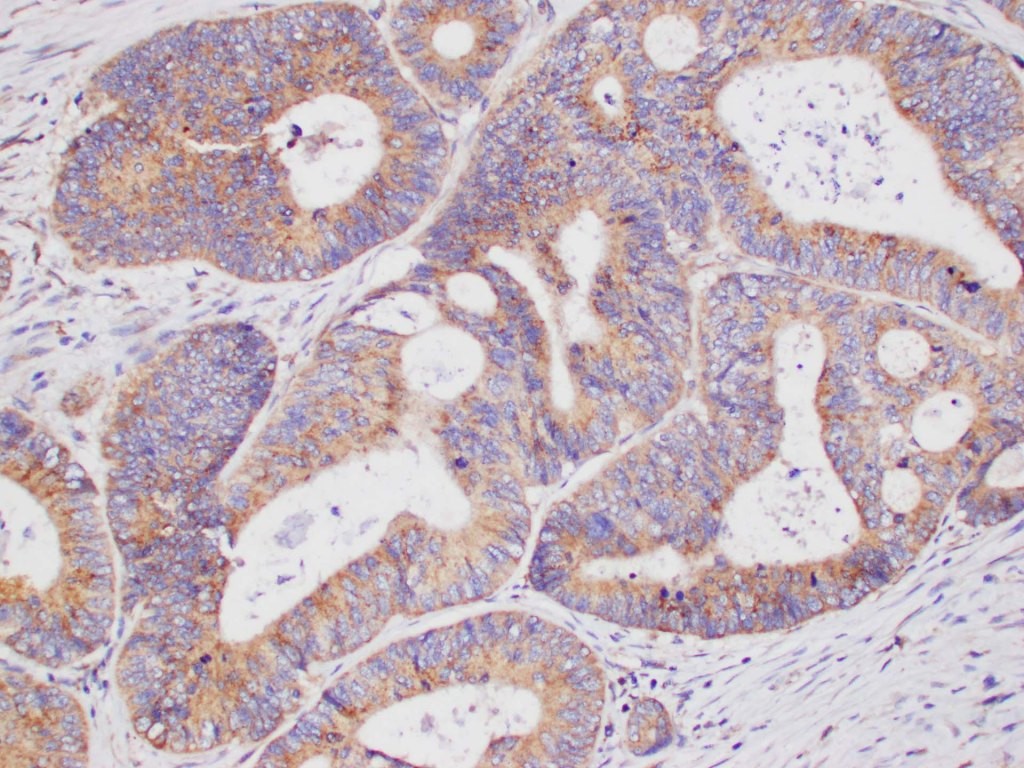

We seek to understand colorectal cancer across the spectrum from normal, to pre-malignancy, early cancer, and metastatic disease.